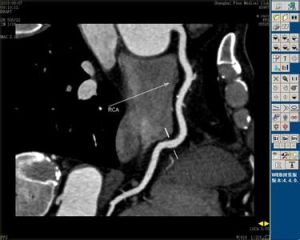

4.冠脈造影(CAG)X綜合徵病人CAG正常或未發現有意義的狹窄,麥角新鹼激發試驗陰性,左心室造影未見異常,無心臟擴大或心肌肥厚徵象,左心室舒張末壓一般正常。

診斷標準:有典型的勞力性心絞痛,發作時ECG有心肌缺血的表現或胸痛不典型,運動試驗陽性,在心室功能及CAG示冠脈正常和麥角新鹼激發試驗陰性,當具有上述各項時,臨床上即可確認為X綜合徵。鑑別